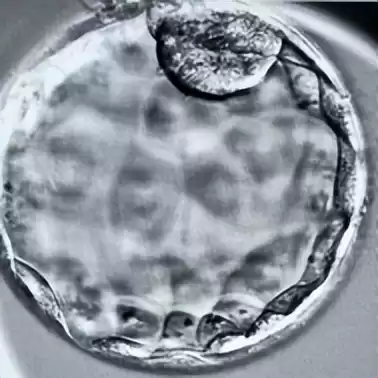

优选胚胎:精挑第2-3天的优质卵裂胚与第5-7天的活力囊胚。胚胎学家严格评估发育潜能,确保只有佼佼者进入冷冻队列。

制胜关键:冷冻前对囊胚人工皱缩,排出多余液体,从源头杜绝冰晶损伤。

降温如电光石火,胚胎内部瞬变“玻璃态”固体,冰晶无处遁形,生命就此完美暂停。

胚胎在-196℃液氮中安然长眠。玻璃化冷冻凭借“脱水保护+瞬间深冻”双保险,为生命按下暂停键,守护万千家庭的生育梦想。